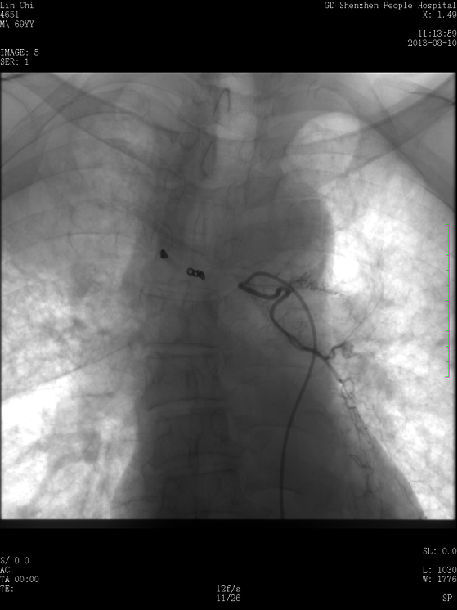

微波消融联合放射粒子植入治疗中央型肺癌

457x610 - 28KB - JPEG